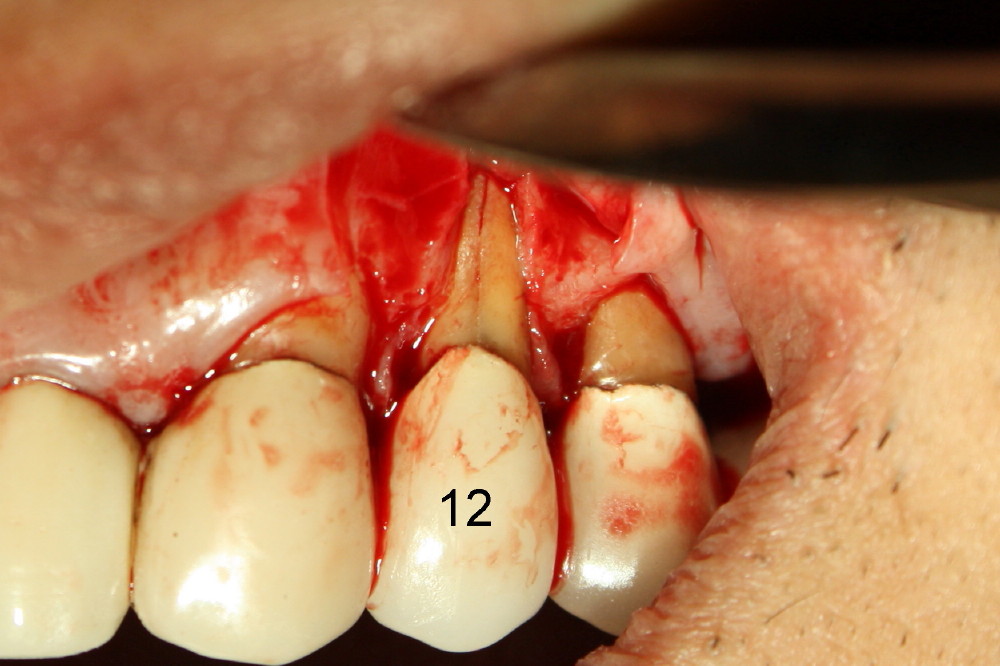

颊侧牙龈沟切口加上附加斜形切口,翻瓣,第一前臼齿(12)根裂,颊侧骨板吸收。

复习病史,可以找到根裂原因:第一,第一磨牙近中根纵裂;第二,前臼齿区疼痛病因不明,可能所有那里治疗都没有必要,根裂可能开始就存在;第三,粗粗牙桩是根裂诱因。